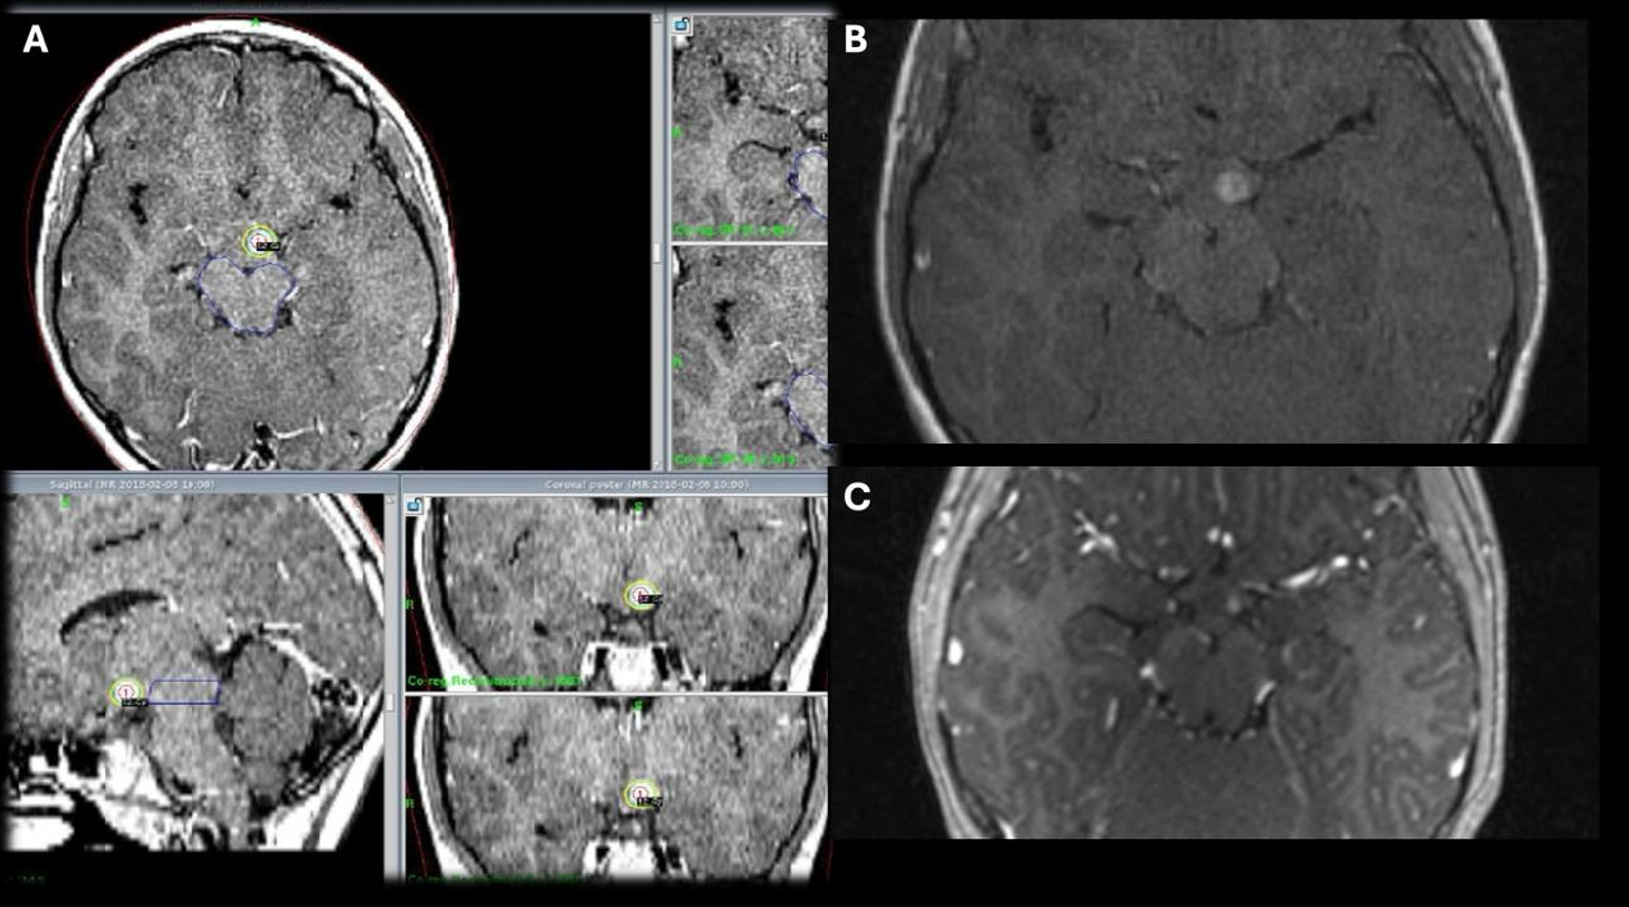

Patolojik tanılara göre değerlendirildiğinde en sık karşılaşılan tümör grubu gliyal tümörler olup, dört hastada saptanmıştır. Bu hastaların ilki 15 yaşındaki kız hasta patoloji sonucu DSÖ derece 3 gliyal kitle olarak raporlanmıştır. Cerrahi sonrası dönemde rezidü kitlesine yönelik lezyon için Karnofsky skoru düşük olması nedeniyle radyoterapi (RT) uygun görülmedi ve hastaya GKRC yapıldı. 5. ay kontrol görüntülemesinde lezyon boyutlarında artış olması ve Karnofsky skoru düzelen hastaya RT yapıldı. Hasta RT’den 2 ay sonra vefat etti. İkinci hasta 15 yaş kız hasta olup patolojisi yüksek dereceli gliyal kitle olarak sonuçlanmış. Karnofsky skoru düşük olduğu için hastaya RT yapılamadı ve GKRC planlandı. 7. ay kontrol görüntülemesinde progresyon izlenen hastanın Karnofsky skor düşüklüğü olması nedeniyle RT planlanmadı ve tekrar GKRC uygulandı. Hasta ilk GKRC tedavisinin 8. ayında vefat etti (Şekil 2). Diğer iki olgudan biri olan 17 yaşındaki kız hastada beyin sapı yerleşimli pilositik astrositoma (DSÖ Derece 1) yönelik hacim bölünerek 18 aylık süreçte 5 farklı seansta ve her tedavide stereotaktik çerçeve yeniden uygulanarak GKRC gerçekleştirildi. 96 ay sonunda lezyonda küçülme izlendi. Bu olguda lezyonun hacmi ve beyin sapı yerleşimi nedeniyle kritik nörovasküler yapılara yakınlığı göz önünde bulundurularak hacimsel evreleme uygulanmış, hedef hacim alt bölümlere ayrılarak farklı marjinal dozlar her bir alt hacme ayrı ayrı planlanmış ve belirli zaman aralıklarıyla uygulanmıştır. 11 yaşındaki erkek hastada ise tektal yerleşimli Diffüz Astrositomun (DSÖ Derece 2) tedavi sonrasındaki 96 aylık takibinde stabil seyrettiği görüldü. Patolojilere göre marjinal doz, takip süreleri ve sonuçlar Tablo 1’de özetlenmiştir.

Düşük dereceli gliyomlar, hipotalamik gliyomlar ve juvenil pilositik astrositomlar gibi iyi huylu pediyatrik beyin tümörlerinde GKRC, cerrahiye alternatif olarak etkili tümör kontrolü ve düşük morbidite oranlarıyla dikkat çekmektedir. Farklı olgu ve hasta serilerinde uygulanan marjinal dozlar genellikle 12-16 Gy aralığında olup, hem kısa vadede hızlı tümör regresyonu hem de uzun vadede progresyonsuz sağkalım sağlamıştır.7,13,17,20,21 24 hastayı içeren çalışmada ortanca tümör hacmi 2,4 cm³ olan ve cerrahi olarak çıkarılamayan ya da nüks eden gliyomlarda GKRC sonrası %71 oranında tümör hacminde küçülme, %21 oranında ise tam gerileme gözlenmiş; 144 aylık uzun dönem takipte progresyonsuz sağkalım oranı %83 olarak bildirilmiştir. Ayrıca, tümör progresyonunun yalnızca büyük hacimli lezyonlarla anlamlı ilişki göstermesi, GKRC’nin özellikle küçük hacimli lezyonlarda etkili olduğunu desteklemektedir.21 Ortalama 2,92 cm³ tümör hacmine sahip diğer düşük dereceli gliyal kitlelerde uygulanan 13,47 Gy ortalama doz ile genel lokal kontrol oranı %89’a ulaşırken, yüksek dereceli gliyal kitlelerde (3,05 cm³ hacim, 17,23 Gy ortalama doz) bu oran %71’de kalmıştır.13 Başka bir çalışmada ise 12 düşük dereceli gliyom olgusuna ortalama 15,2 Gy uygulanmış 2 hastada progresyon izlenmiş, 12 yüksek dereceli gliyomda ise ortalama doz 18,8 Gy, takiplerinde 6 hastada progresyon görülmüştür.23